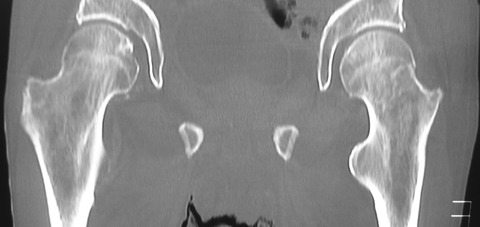

CTでは左腎背側に筋欠損部が存在し、そこから筋層外に腎周囲の脂肪織と思われるlow density massの脱出を認めではないですか!

おかしいなぁ と思いながらも脂肪腫ならば、とMRIを依頼しました。しかし、MRIの画像を確認すると明らかに背筋が欠損しており、腫瘤は後腹膜の脂肪組織と連続していました。

外科医師に相談すると、これは特発性の「上腰ヘルニア」ではないかとのことでした。患者さんの腰背部腫瘤を触知すると、患者さんの発声が腫瘤を通じてダイレクトに私の手に伝わります。